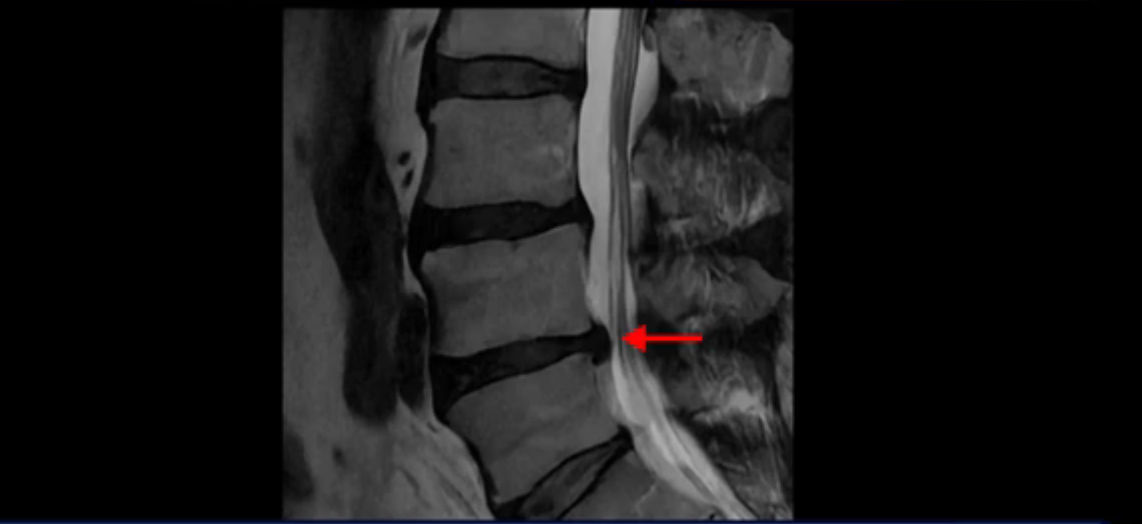

그런데 이분은 4번 5번에도 디스크 파열이 있습니다.

가운데로 심하게 밀려 나와 있는데요.

또 4번 5번에는 협착으로 척추관이 많이 좁아져 있습니다.

또 왼쪽 신경 가지들이 빠져 나가는 신경구멍들이 여러 마디가 좁아져 있습니다.